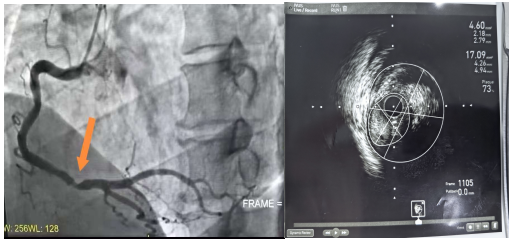

1. 避免过度治疗:患者章某因急性心梗接受急诊手术后,IVUS精准测量显示其右冠脉狭窄处管腔面积达4.60mm²(指南标准无需支架),避免了不必要的支架植入,改为强化药物治疗。

溶栓抗凝后复查造影结果 IVUS检查结果